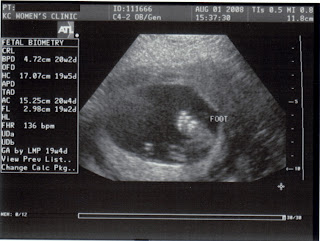

We went to the doctor for our 19-week ultrasound today and although the baby was stubborn and overly modest, the ultrasound tech was able to tell that we're having a boy! Everything looks good, size is healthy, and we could actually see the spine, 4 heart chambers, and bones. It was really cool!

We're pretty sure this is the heart. The band below is the heartbeat tracker (136 bpm); all the little peaks are individual heartbeats.

Big giant foot: